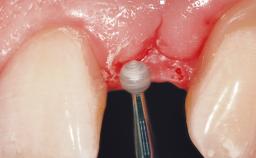

A 36-year-old female patient was referred for the replacement of the upper left central incisor (tooth 21), which had fractured. Although the tooth had been asymptomatic for many years, the crown began to loosen, at which time she presented to her dentist for an assessment. Teeth 21 and 22 had both been endodontically treated many years previously. She was a healthy individual and a non-smoker.

| Soft Tissue Grafting | Simultaneous |

| Soft Tissue Contour and Volume | Slightly compromised |